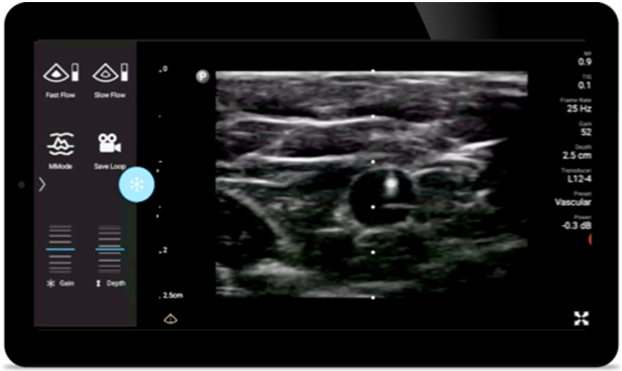

Lumify helps you clearly visualize needle placement, surrounding nerves, vessels and fascial planes.

Lumify handheld ultrasound for anesthesiology helps you clearly visualize border definition with your needle placement, surrounding nerves, vessels and fascial planes.

Lumify L12-4 broadband linear array transducer

• 12 to 4 MHz extended operating frequency range

• Aperture size: 34mm

• 2D, steerable color Doppler, M-mode, advancedXRES and multivariate harmonic imaging, SonoCT

• High resolution imaging for shallow applications: soft tissue, vascular, superficial, musculoskeletal and lung

• Center line marker

• USB-C transducer with replaceable cable